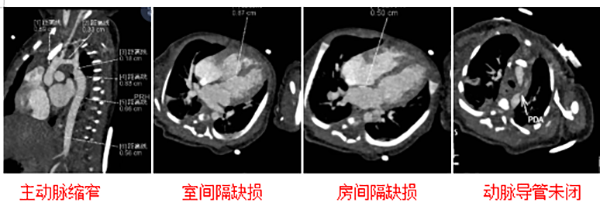

出生仅19天、体重仅3公斤的梦梦(化名),刚来到这个世界,就面临一场生死大考——她的心脏主动脉最窄处只有1.8毫米,还同时合并了三种心内畸形。用医生的话说,“就像生命的主干道上,被人接连设下了好几道致命路障”。

转诊到上儿贵州医院后,检查结果让所有人心头一紧:梦梦的主动脉弓到降主动脉起始部弥漫性狭窄,最窄的地方只有1.8毫米。

1.8毫米是什么概念?接诊医生解释道,“这一直径甚至不足正常新生儿主动脉的1/5。这犹如在生命主干道上设置了致命路障,导致上半身高血压,下半身缺血缺氧,即使心脏拼命工作却徒劳无功。”

更棘手的是,除了主动脉狭窄,梦梦还同时合并室间隔缺损、房间隔缺损、动脉导管未闭,三种心内畸形,一个都没落下。

最终,在手术团队的紧密配合下,手术顺利完成——中低温体外循环下,主动脉缩窄矫治、室间隔缺损修补、房间隔缺损修补、动脉导管未闭缝扎,四个操作一次完成。